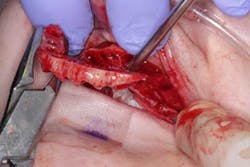

Surgery commenced. Implants on the lower arch were placed first (figures 7 and 8) and then we switched to the maxillary. The teeth were removed (figures 9 and 10) and the ridge was evened out (figures 11-13). The implants were aligned with the denture (figure 14) and then placed accordingly (figures 15-17). Healing caps were put on, and we were ready to start the restorative phase (figures 18-19).